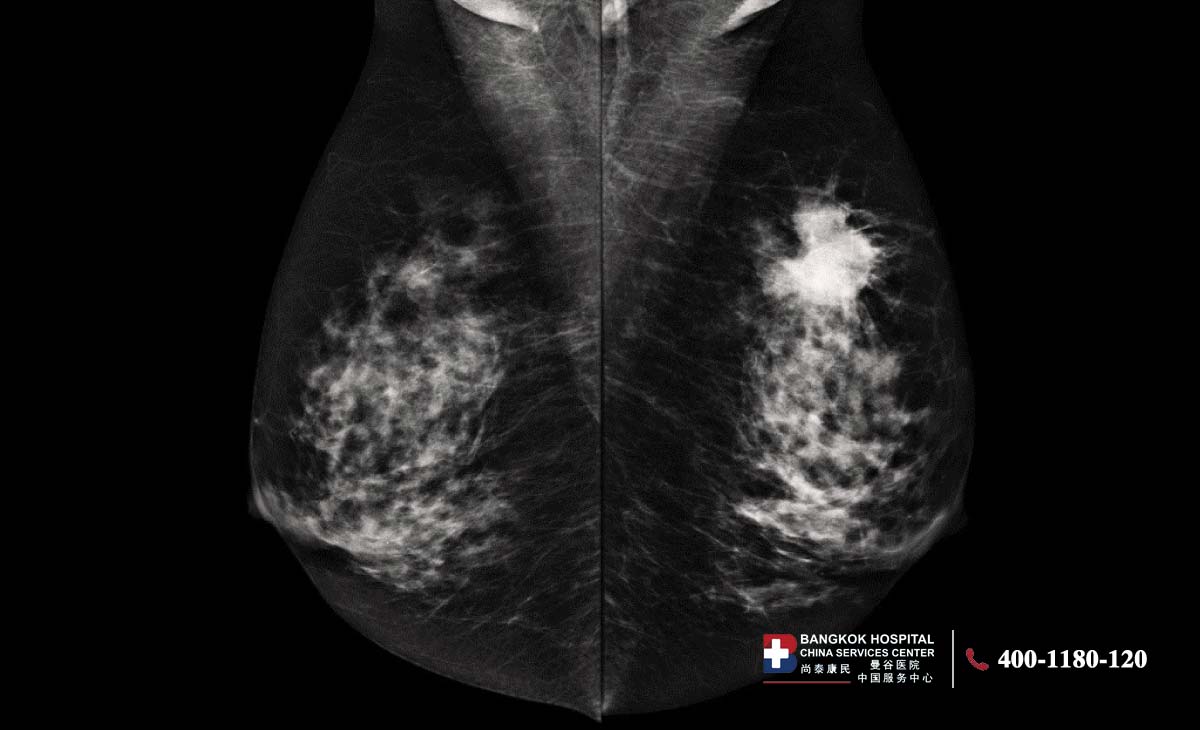

对比增强乳腺X线摄影(CEM)自2011年起获得美国食品药品监督管理局批准上市。大量研究证实了该技术的临床应用价值,其在国际上的应用也日益广泛。该检查需注射含碘对比剂,并采用双能X线成像技术对乳腺进行数字化X线摄片。设备会分别采集低能和高能两种能量下的影像,再经处理生成重组图像。这项技术能够清晰显示乳腺组织中的可疑病灶,提示可能存在的异常血供或乳腺癌病变。CEM在成像原理上与乳腺磁共振(MRI)相近,相较于常规乳腺X线摄影准确性更高,尤其适用于乳腺致密型人群。

曼谷癌症医院乳腺中心、乳腺影像诊断专家Dr.Khwansakul Boonsararuxapong表示,CEM是一种结合造影剂和乳腺X光的影像检查技术。检查时医生会先注射造影剂,再通过双能量X光成像,让乳腺中的异常血管或可疑病灶更加清晰地显示出来。